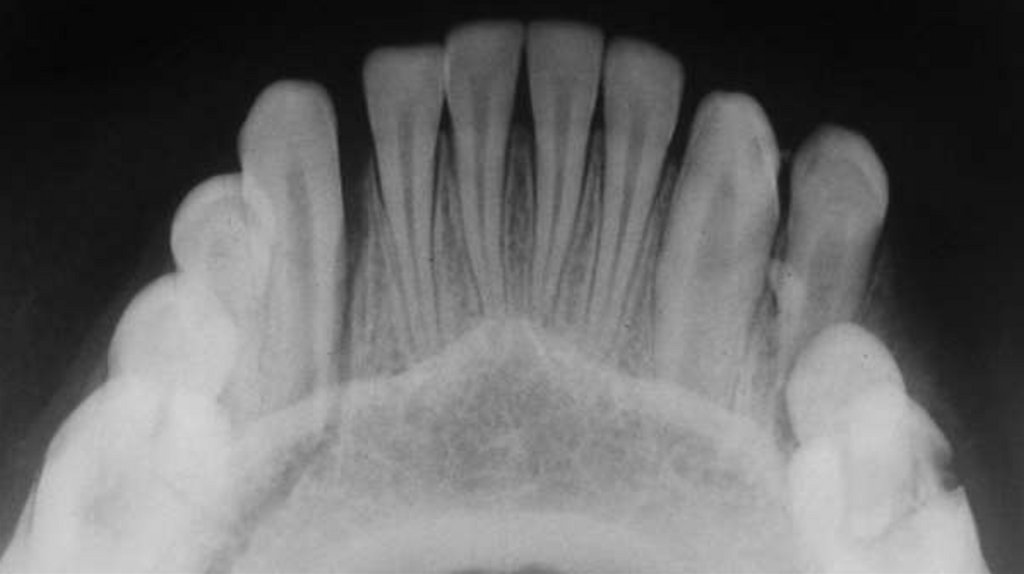

Были собраны подробные истории болезни, проведены

клинические и рентгенографические исследования, такие как

ортопантомография, окклюзионная рентгенография и

внутриротовая периапикальная рентгенография . После

тщательной оценки был поставлен диагноз типа перелома и был

составлен план лечения для каждого пациента.

Послеоперационные рентгенограммы были получены для

подтверждения заживления места перелома перед удалением

шины (рис. 5 и рис. 8), и все пациенты наблюдались в течение 12